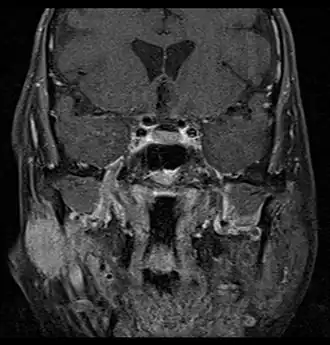

Parotid gland tumour

MRI or CT Scan: These tests can confirm the presence of a tumour. An MRI or CT Scan can also show whether metastasis has occurred.[4]